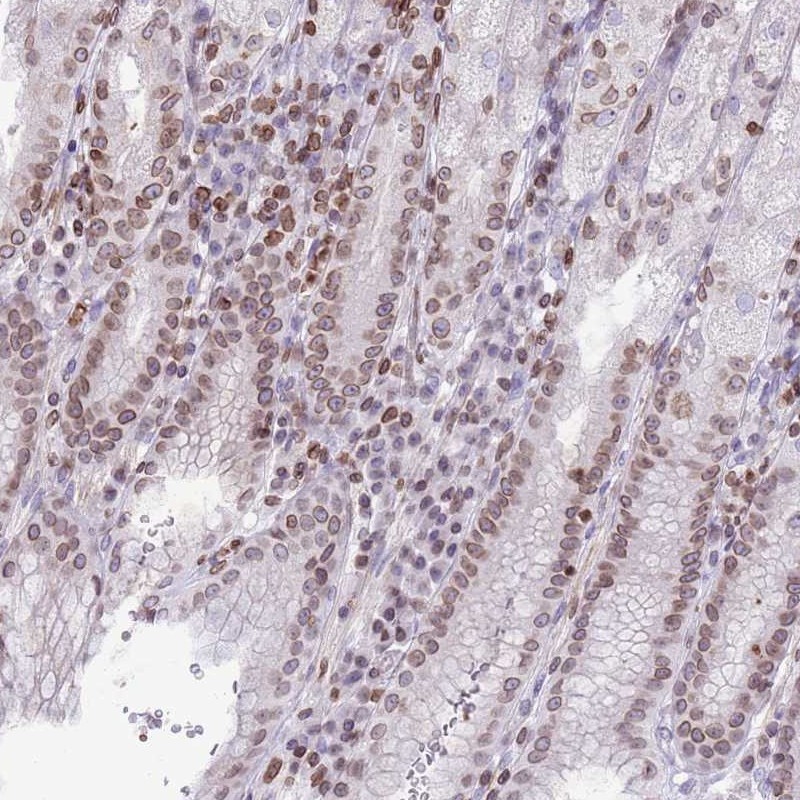

Immunohistochemical staining of human stomach shows moderate nuclear positivity in glandular cells.